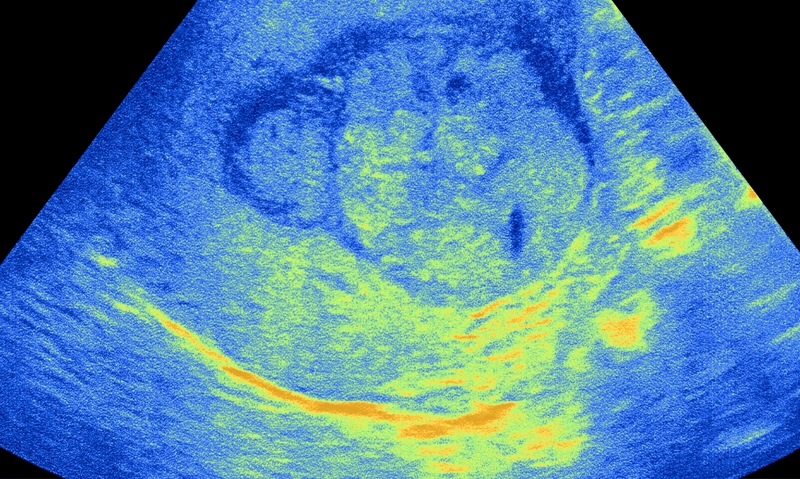

Patients attending the public liver clinic were offered 6-monthly ultrasounds scans and serum alpha-fetoprotein (AFP) tests if they had cirrhosis or if they were high risk and non-cirrhotic.

Professor Geoff McCaughan, head of the liver injury and cancer group at Sydney’s Centenary Institute, said a more cost-effective surveillance option than outreach sonography as suggested in the latest study might be 6-monthly testing for serum AFP levels.

“A blood test would seem a cost-effective outreach option”, he said.